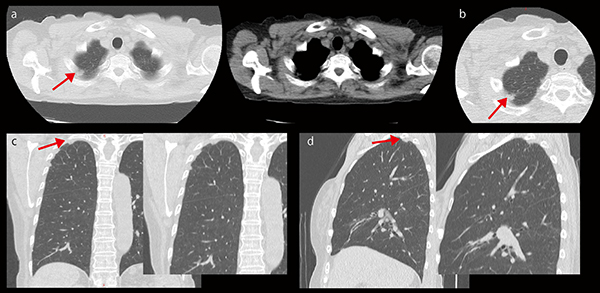

■Aquilion Lightningによる低線量肺がんCT撮影

a:アキシャル画像 b:HRCT c:コロナル画像 d:サジタル画像

アキシャル画像で右肺尖部に11mm×8mm大の非石灰化結節を認める。HRCTで肺がんの否定ができないが、コロナル画像、サジタル画像を追加することで胸膜の限局性肥厚で、陳旧性胸膜炎像と診断できた。本検査においても低線量撮影を行っているが、AIDR 3D Enhancedにより肺尖部のストリークアーチファクトが低減され、視認性が向上している。